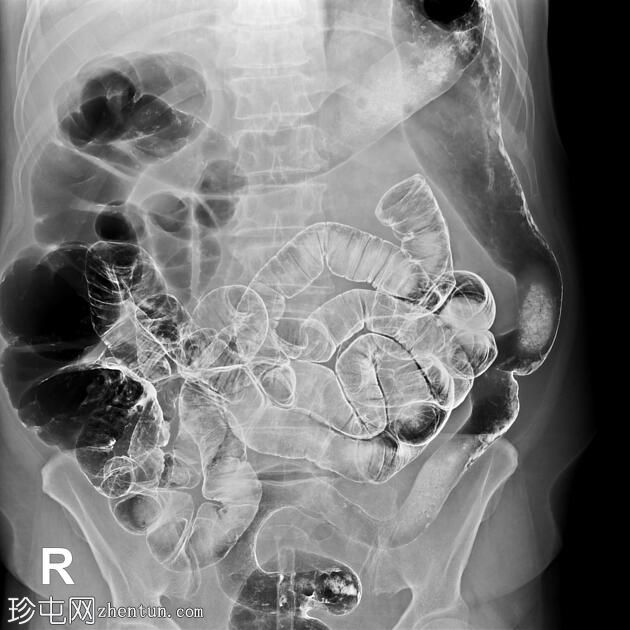

冠状位

结肠异常表现包括结肠袋皱襞消失,使其外观模糊,呈铅管样改变。

其他异常表现包括降结肠和乙状结肠肠袢狭窄,以及横结肠和降结肠多处黏膜糜烂(双对比增强图像可见)。

未见肿块或瘘管形成。

升结肠外观正常,结肠袋皱襞完整。